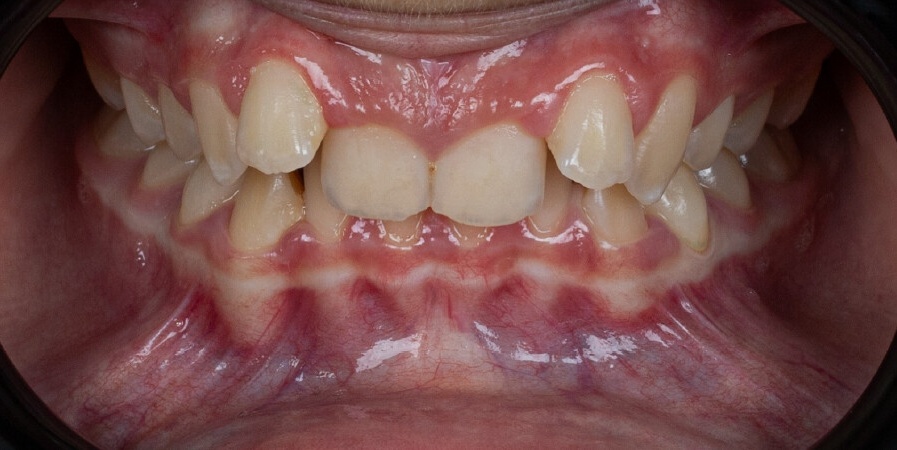

Un paziente di 13 anni con malocclusione di classe II divisione 2 e morso profondo è stato trattato utilizzando Angel Aligner A6 Mandibular Advancement. Il protocollo ha combinato l’avanzamento mandibolare, l’espansione dell’arcata, l’intrusione degli incisivi e il perfezionamento con elastici di classe II, ottenendo una correzione funzionale del morso e un miglioramento dell’estetica del sorriso in 10 mesi.